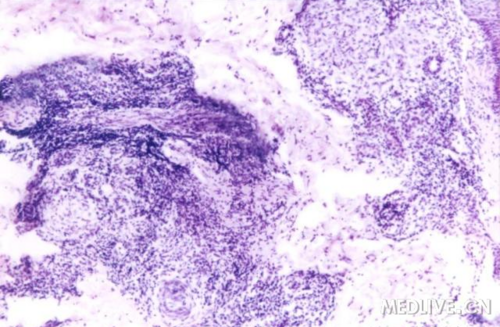

http://webres.medlive.cn/upload/000/026/064

粟粒性狼疮结核样结节 HE X4